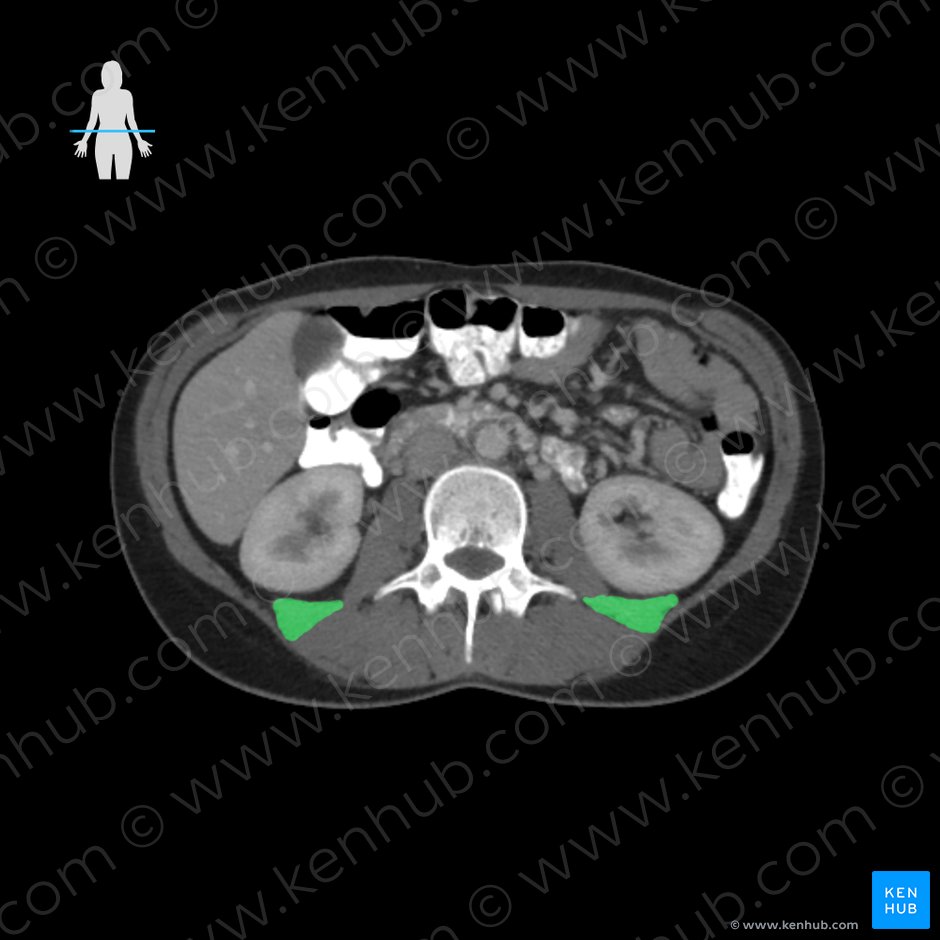

(좌측 신장은 L2, 우측 신장은 L3 level에 위치)

대요근 : 초록색, 장요근: 분홍색 (1) 대요근(psoas major)

origin: 전방부- L1-L5 척추체와 디스크의 옆면

후방부- T12-L4까지 횡돌기의 전면

(Vertebral bodies of T12-L4,

intervertebral discs between T12-L4,

transverse processes of L1-L5 vertebrae)

장요근은 척추체에서 시작되는 대요근과

골반 안쪽에서 시작하는 장골근 두 근육이

하나로 합쳐져 대퇴골 소전자에 부착하는 근육입니다.